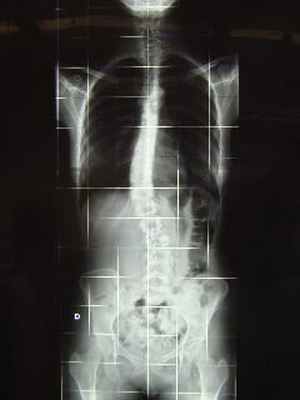

Сколиограмма или рентген всего позвоночника

Для диагностики и контроля идиопатического сколиоза необходимо увидеть весь позвоночник на одном снимке в профиль и анфас.

Сколиограмма в анфас